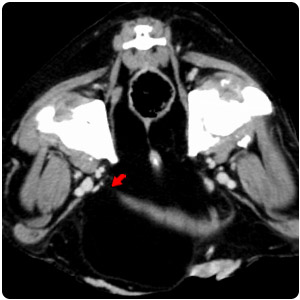

| 右耳腫塊 耳道鼓室泡填塞 |

側腦室非對稱性中度擴張

第三四腦輕微擴張 |